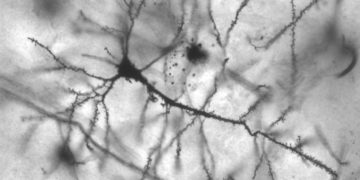

Leggi di piùSi chiamano CD22 e COL17A1 e non sono i nomi di due robot di Star Wars bensì di due geni...